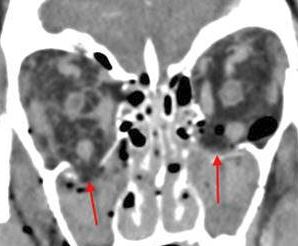

21-year-old male in the emergency room following an altercation with possible orbital or other facial fractures.Exam

There is evidence of blood products in the paranasal sinuses. |

Yes | NA |

There is evidence of herniated intra-orbital fat. |

The extraocular muscles are swollen, infiltrated or herniated into a fracture site. |

There is evidence of bony injury along the walls and/or floor of the orbit. |

The mesial naso-orbito-ethmoid complex is fractured. Specifically, there is bony injury of the nasal bones or the frontal process of the maxilla and the medial walls of the orbit are abnormal. |

Orbital floor fracture on the left with significant entrapment of orbital fat and entrapment of the inferior rectus muscle in a likely trapdoor type mechanism and minimally displaced fractures of the medial orbital wall and nasal bones.

Contact ER providers verbally about the finding of likely “trapdoor” herniation of the inferior rectus muscle and strongly suggest the ophthalmology and facial trauma on call be consulted emergently with regard to this finding.